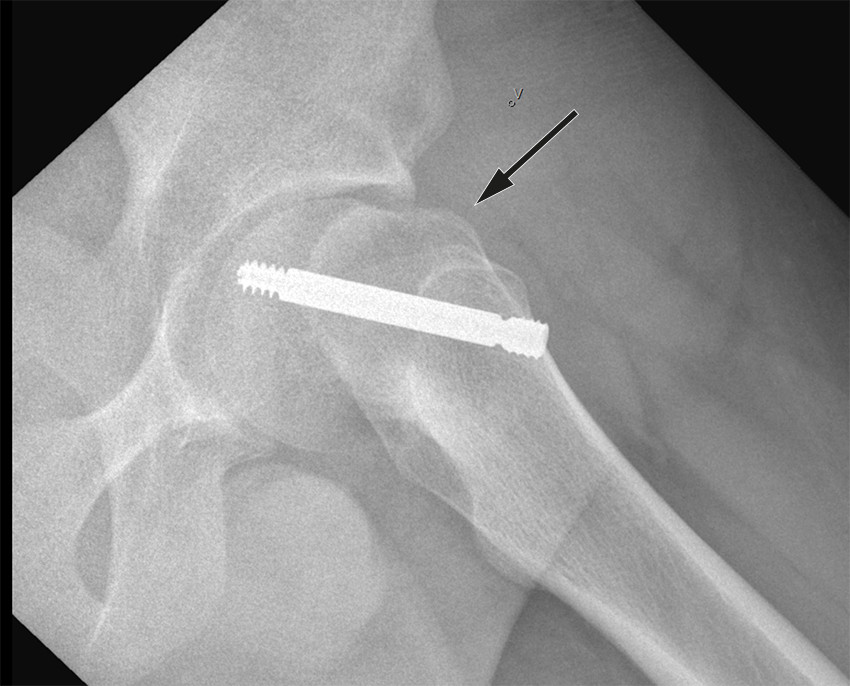

Standard behandling er operativ stabilisering av epifyseskiven. Hensikten er å gjøre pasienten symptomfri samt hindre ytterligere glidning. Epifyseskiven stabiliseres in situ, det vil si man gjør ingen forsøk på å reponere glidningen. Imidlertid vil en del av feilstillingen kunne reponere seg spontant ved ustabil epifysiolysis capitis femoris i forbindelse med leiring under operasjon (figur 2). Grunnen til at det ikke skal gjøres noe aktivt forsøk på reponering er at det gir økt risiko for skade på blodforsyningen til epifysen, med fare for caputnekrose som komplikasjon (11).

Prosedyren er perkutan, har få komplikasjoner og krever kortvarig innleggelse. Vi anbefaler at det benyttes skrue som tillater fortsatt vekst i epifyseskiven, da dette vil fasilitere remodellering samt redusere benlengdeforskjell (12). Man trenger ikke å fjerne skruen senere med mindre den gir kliniske plager.